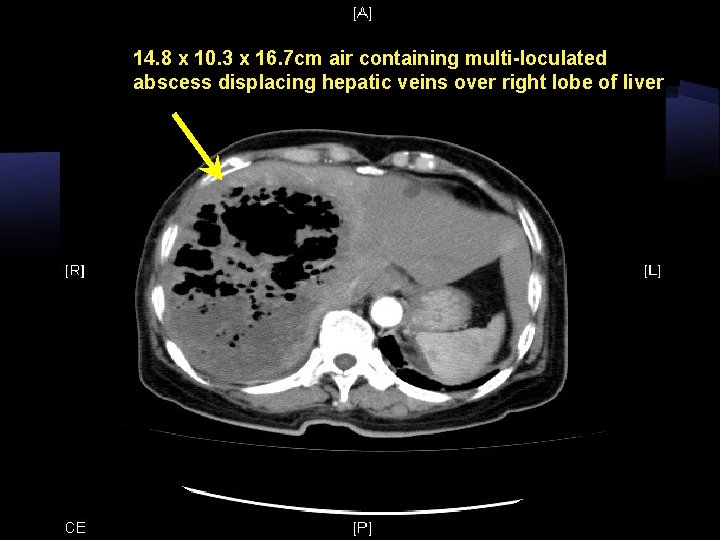

F/73 Poorly controlled DM Admitted for fever, deranged LFT USG: Gas containing liver abscess

14. 8 x 10. 3 x 16. 7 cm air containing multi-loculated abscess displacing hepatic veins over right lobe of liver